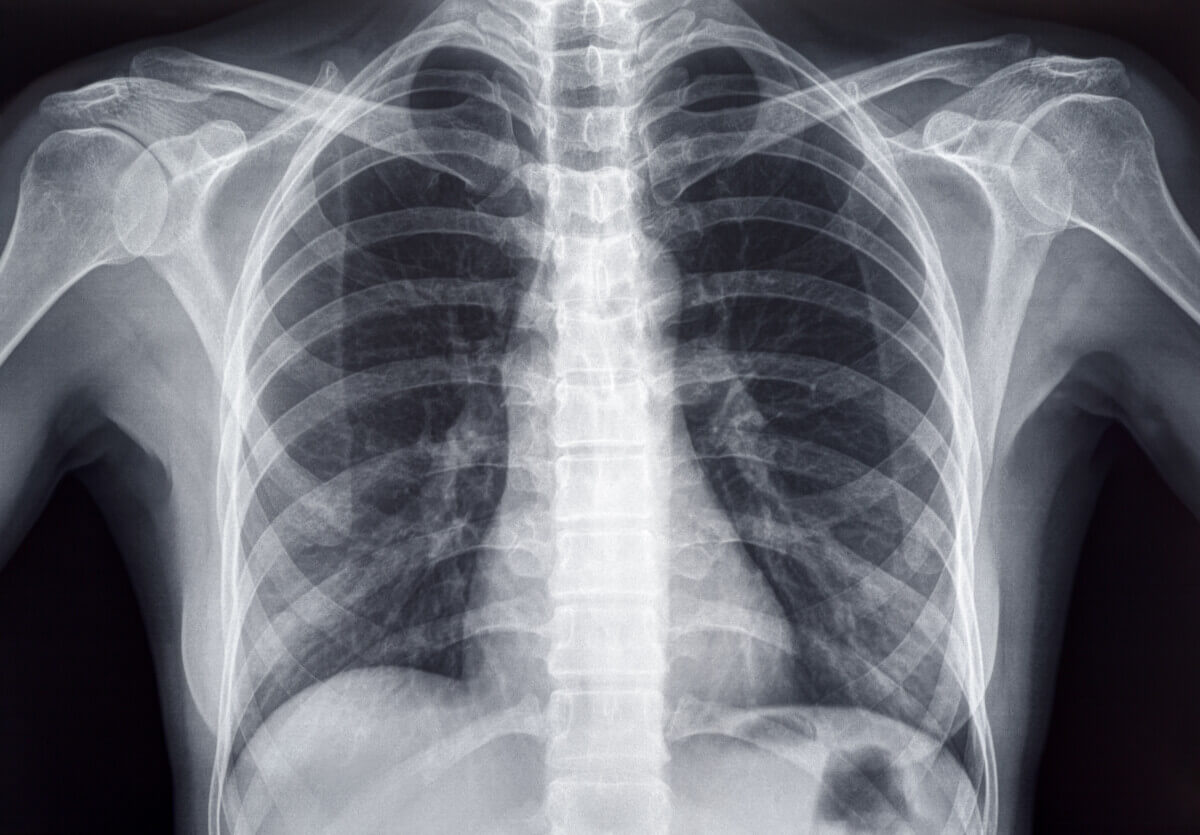

Chest X-ray of an Adult Female Human (© PhotoEdit - stock.adobe.com)